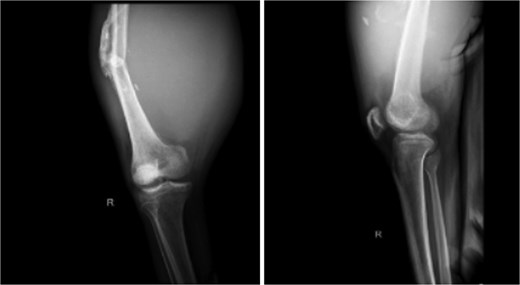

X-ray imaging of the right femur reveals a mid-shaft fracture with prominent callus formation. A soft tissue mass is observed surrounding the right femur, with no evidence of underlying bone lesions.